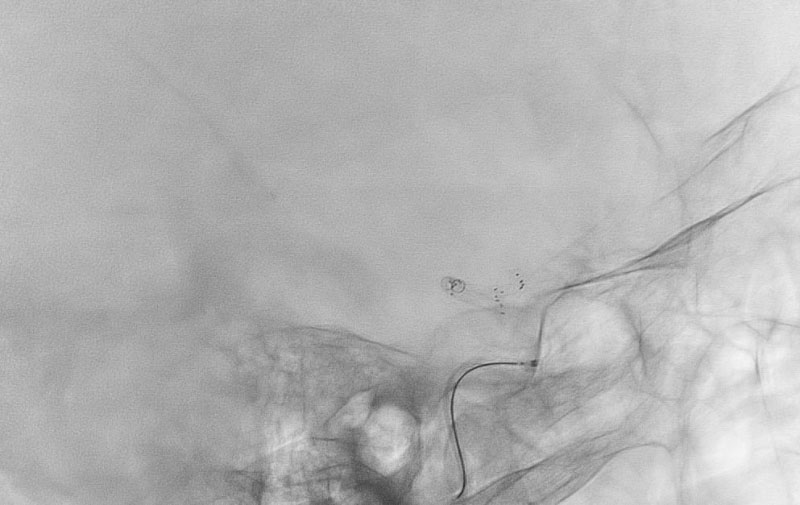

くも膜下出血

左中大脳動脈瘤破裂

40代

救急外来

No.1596 手術中